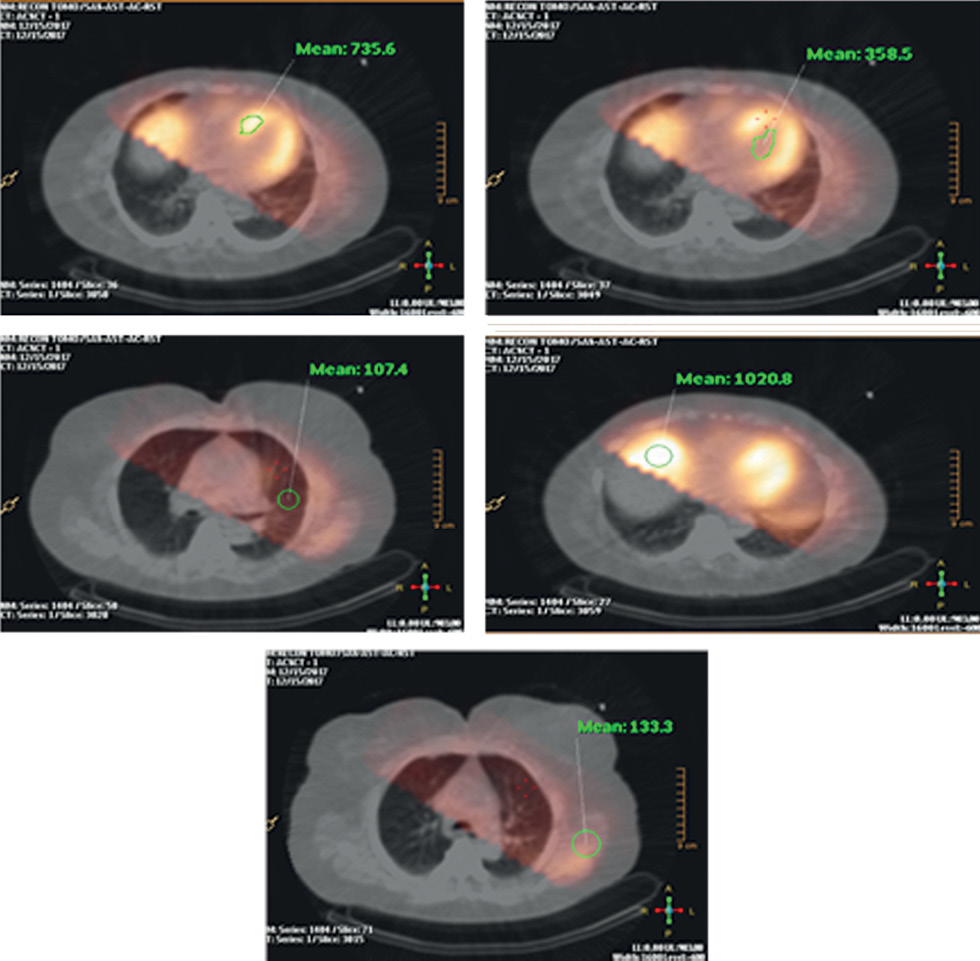

The distribution of radiopharmaceuticals in various organs, rather than the anatomical structure of the patient, plays a critical role in nuclear medicine simulation studies. The virtual patient program generates a 3D map of radiopharmaceutical uptake (“activity map”) in the MMT phantom using clinical data on the distribution of 99mTc-MIBI. As an example, Fig. 2 shows clinically reconstructed SPECT images of a real patient, with activity values in several organs in pulse/voxel units. Data were collected using SPECT/CT imaging (Philips BrightView XCT, Philips, Netherlands) at the EI Chazov National Medical Research Center of Cardiology. These values may differ among patients. The present study used the values shown in Table 1 when creating an activity map for the MMT phantom. A homogeneous distribution of activity within each organ was specified, except for modeling LV myocardial ischemic injury.

Fig. 2. Clinical data. Relative values (pulse/voxel) of accumulation of the radiopharmaceutical 99mTc-MIBI in the patient’s chest organs. The images were obtained during examination of the patient using single-photon emission computed tomography combined with computed tomography using a Philips BrightView XCT installation at the Federal State Budgetary Institution “National Medical Research Center for Cardiology named after Academician E.I. Chazov" of the Ministry of Health of the Russian Federation.